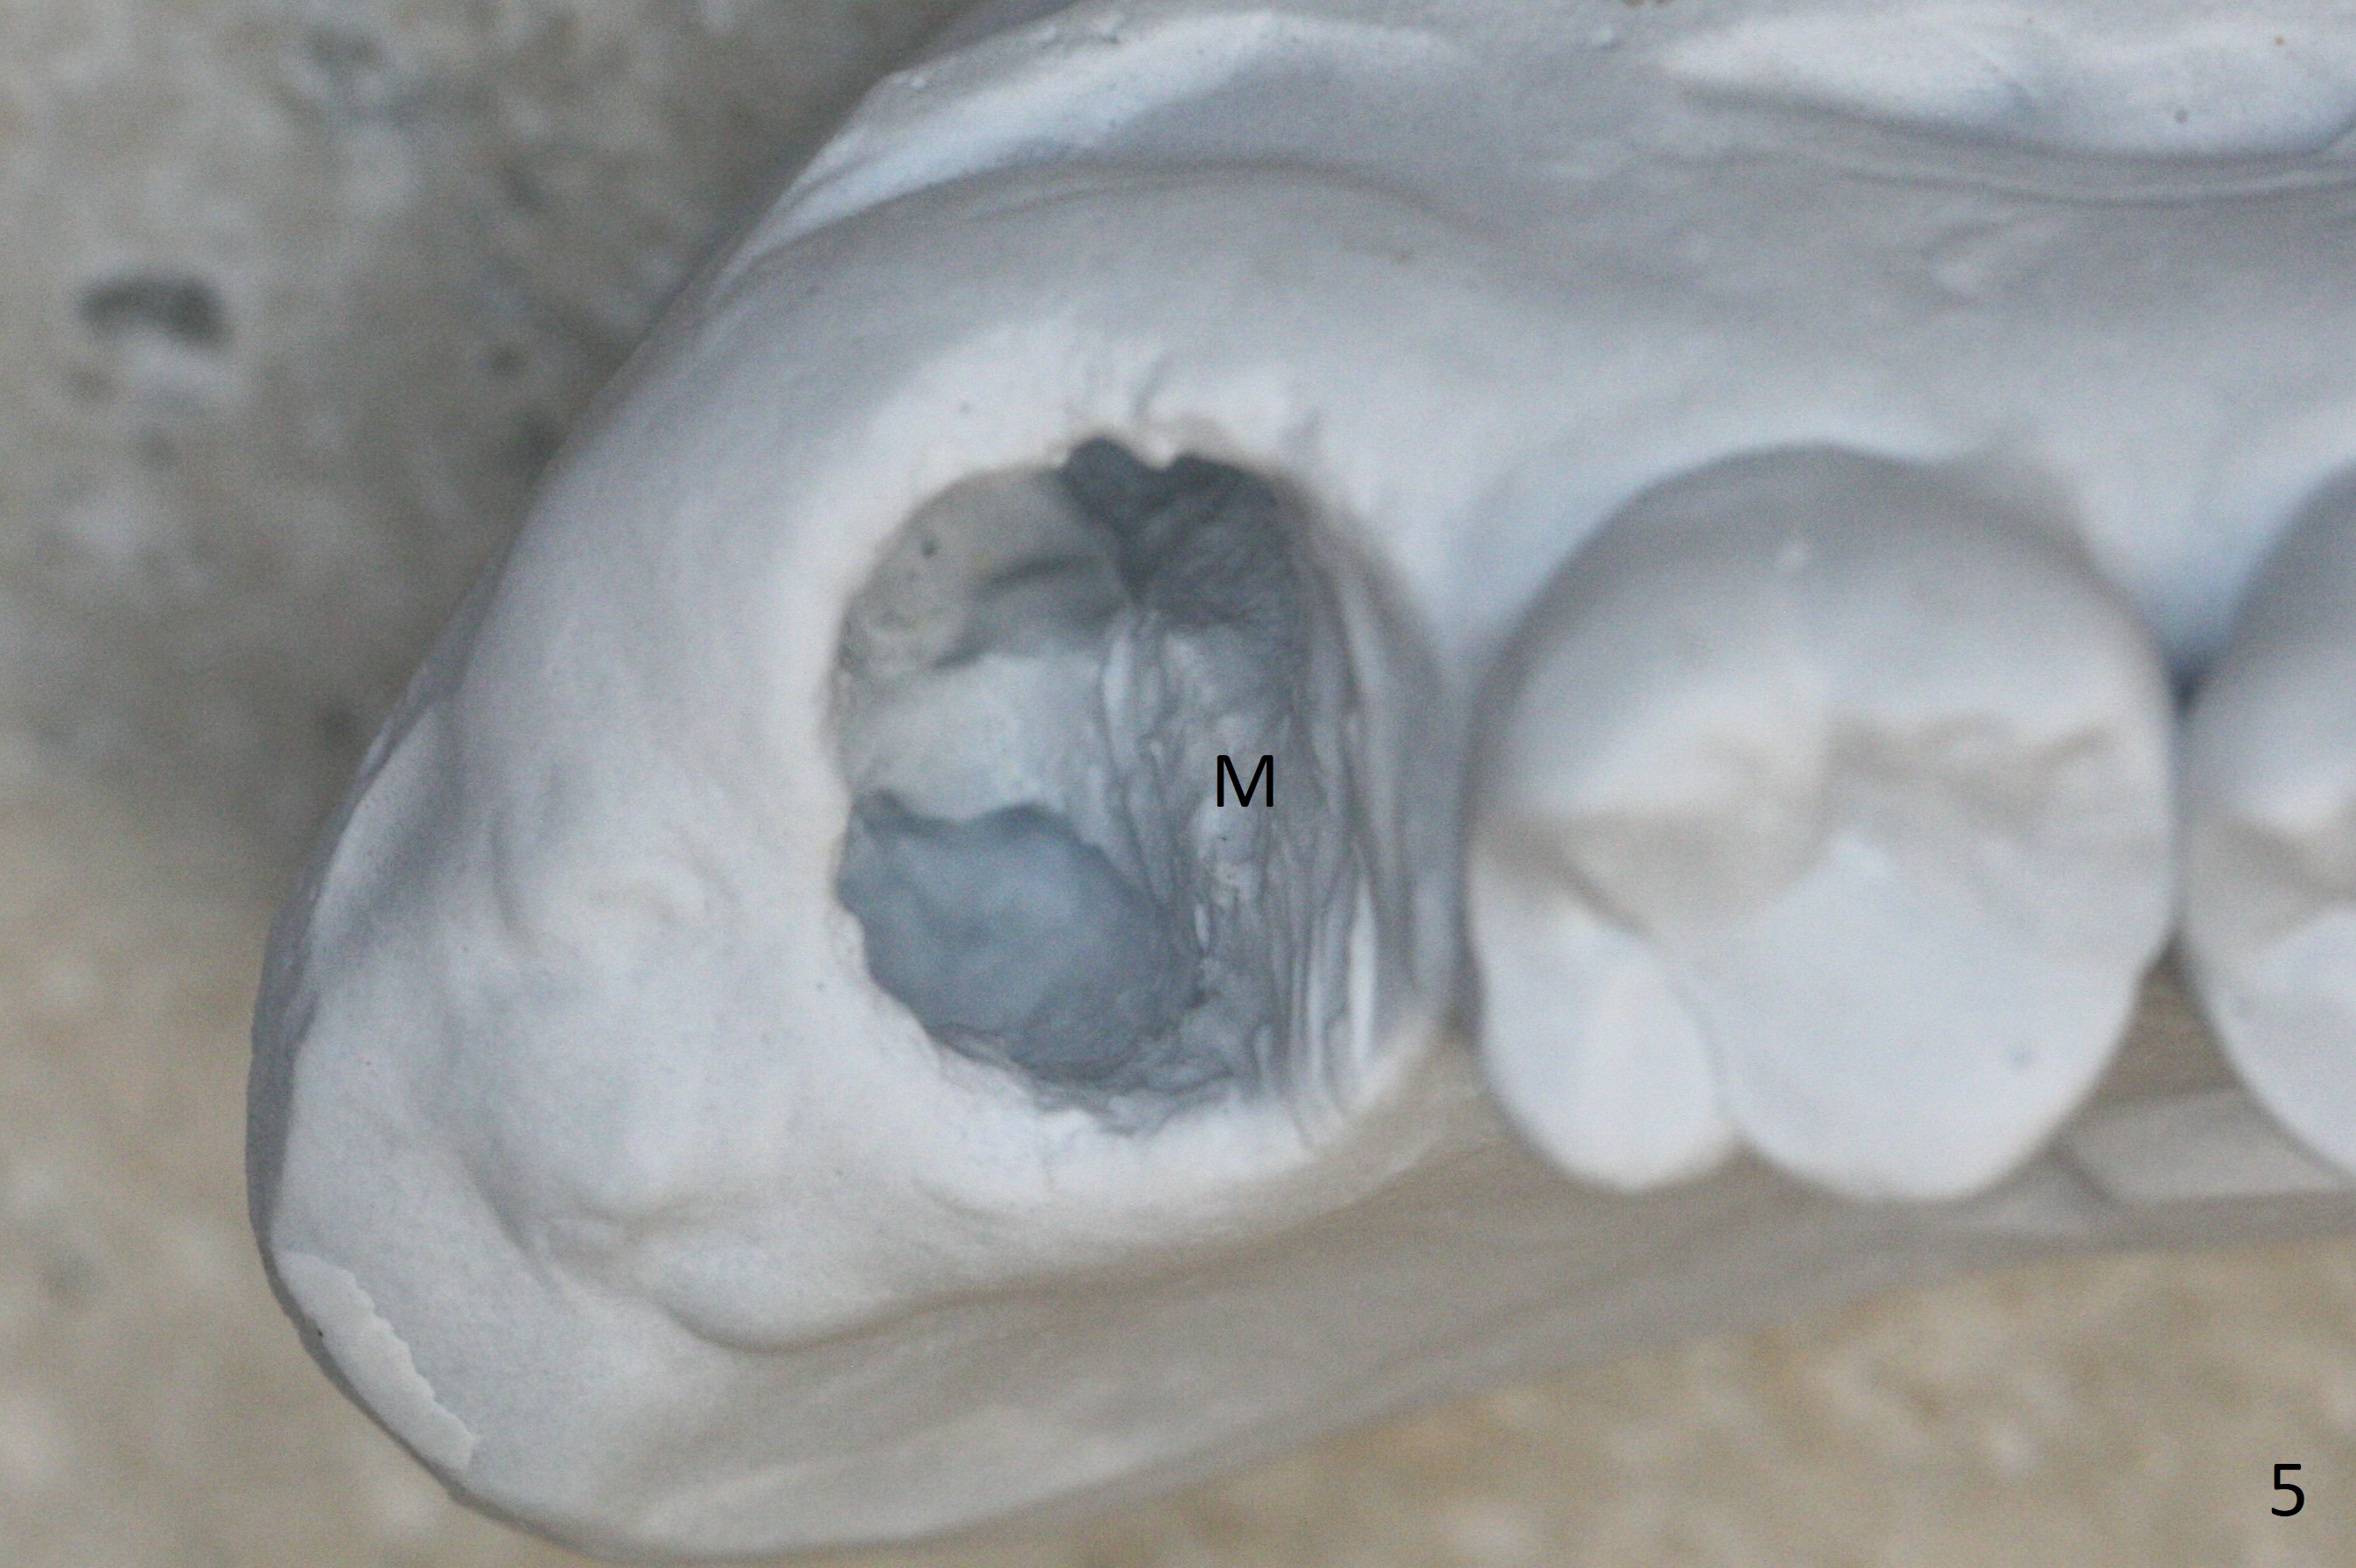

Fig.5 shows the mesial slope of the socket (M), which is more or less the center of the socket mesiodistally. If the osteotomy were set up in the red circle (Fig.6) in the mesial slope (Fig.8 green dashed line), the trajectory of 4.5x11 mm dummy implant (Fig.7) would be more ideal (Fig.8 red outline) with more native bone contact. Finally a longer IBS implant is placed (4.5x15 mm, Fig.9,10) to achieve primary stability (50 Ncm). When the provisional is removed for impression 3 months 10 days postop, the implant is found to have been placed distopalatally (Fig.13), which should have been avoided. It appears essential to use guide for a distal implant. It is agonizing to re-encounter the off-axial implant (Fig.14) and the distopalatal access hole (Fig.15) 1 year post cementation. It is also amazing that the abutment screw has not loosened. A fair-sized piece of bone graft has just been removed buccally (Fig.15,16). The patient complains of sensitivity 2 years 3 months post cementation, although there is no abnormality around the implant crown. Guided surgery is essential to avoid restoration complication. There is no thread exposure nearly 3 years post cementation; in fact the apical portion of the abutment is covered by the bone (Fig.17,18).